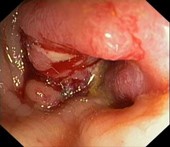

Рак |